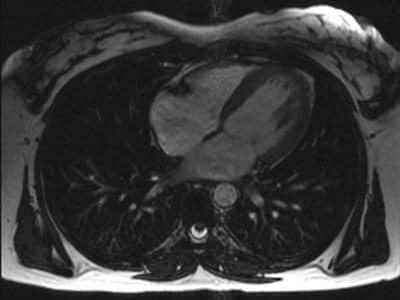

„Ši technologija leidžia diagnozuoti ligas ankstyvoje stadijoje ir tiksliai įvertinti širdies raumens būklę. MRT aiškiai parodo skilvelių judesius, uždegimo ar edemos židinius, fibrozę ir randus po infarkto“, – sako Ernestas Kaminskas, sveikatos sprendimų centro „Antėja“ Radiologijos skyriaus vadovas.

MRT suteikia informaciją, kurios kartais nepavyksta gauti įprastais tyrimo metodais. Pavyzdžiui, širdies echoskopijos galimybes gali riboti paciento anatomija ar techninės sąlygos. Kompiuterinė tomografija puikiai tinka vertinant kraujagysles, tačiau ne visada aiškiai atskleidžia audinių pokyčius.

Širdies MRT leidžia įvertinti, ar širdies audinys yra gyvybingas, ar jame vyksta uždegiminiai procesai, ar jau susiformavę randai po infarkto. Tokia informacija dažnai lemia tolesnę gydymo taktiką ir padeda parinkti tinkamiausią gydymo planą.